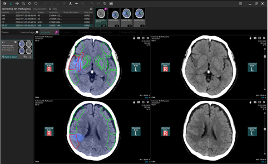

Ischemia analysis |

・Ischemia analysis

・Hemorrhage analysis

・Brain Vessel Occlusion

・MR DWI/FLAIR Measurement